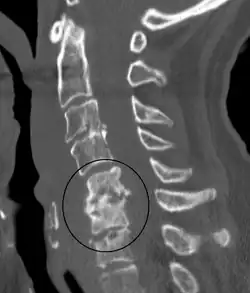

| Discitis in a 2 year old child. | |

Diagnosis is usually apparent on MRI, although plain X-rays and CT examinations can be suggestive. The MRI will reveal air changes in the disc and possibly even external involvement involving the bone or epidural regions. A biopsy may be performed and helps with diagnosis in some cases but often an organism is not obtained. C-reactive protein levels and ESR levels will be elevated and are useful for treatment. The white blood cell count may be normal.[5][6]